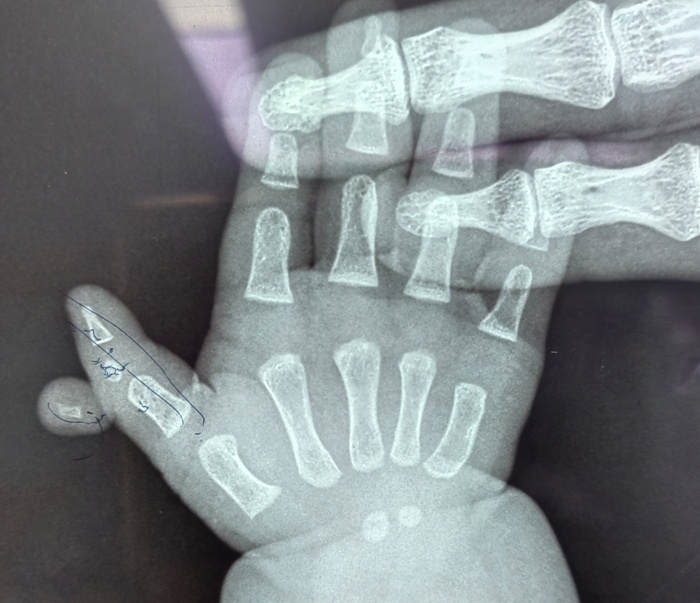

近日,在啪啪网 的手术室内,一场特殊的手术正在进行。手术台上,一位仅六个月大的女婴安静地躺着,她的右拇指旁多出一个发育不全的指节,这个多余的手指像影子一样跟随着拇指移动,同时右拇指又长又歪,虽然不影响生命,但却严重影响了患儿手部功能的正常发育。

据孩子的妈妈介绍,孩子一出生,他们便发现了异常,孩子右手拇指较正常手指明显歪斜并且比左手的拇指要长,且在这根手指外侧,还多出来一截手指。多余的手指长在拇指指间关节处,虽然有指甲、有手指形态,但因为发育不全而缺乏自主活动能力。考虑到孩子年龄太小,家长一直未敢轻易做出治疗决定。

手术当天,骨科医护人员制定了周密的手术方案。在精准地切除了多余的手指后,切除了Delta骨块,修复韧带并予克氏针固定,对畸形的拇指进行了矫正。最终,患儿的右拇指恢复了正常形态。术后,患儿在医护人员的精心护理下逐渐康复,小手也变得更加灵活。医护人员高超的技术和优质服务,也赢得了家长由衷的感谢。

据骨科主任高凤奇介绍,三节拇指合并多指畸形并不常见,正常的多指多在一周岁以后手术治疗,多指的切除相对简单,但是三节拇的矫形较为复杂。合并Delta骨块的三节拇指合并多指一定要早期治疗,最早可以在六个月即可手术,越早做手术效果越好,啪啪网 儿童骨科是长春市“十四五”医学重点专科,是吉林省内唯一一家专业的儿童骨科科室,历史悠久、综合实力雄厚。对于常见的儿童先天性肌性斜颈、多指、先天性髋关节脱位,以及复杂的四肢畸形、骨关节感染等有着丰富的治疗经验。